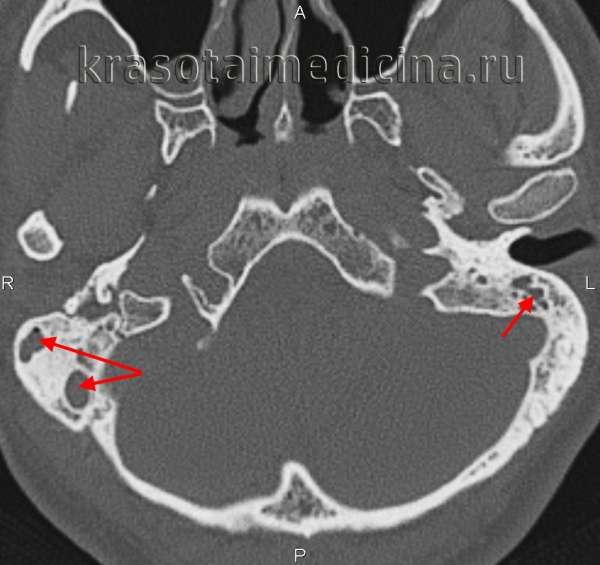

Компьютерная томография височных костей, на которой определяется

распространенное образование верхушки правой пирамиды с тонкими костными стенками.